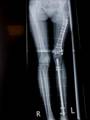

Follow Up

Left tibia lengthening with fixator in place

Lengthening tibia on Xrays in progress

Lengthening proceeding

Converted to immediate exchane nail after 65mm lengthening

Consolidation regenerated

Leg length equalised but with different knee height